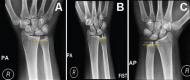

Methods: This 6-month (December 2013 to June 2014) cross-sectional study was conducted on a randomly selected healthy adult volunteers with a sample size of 104, at King Abdulaziz University Hospital, Jeddah, Saudi Arabia. Posteroanterior (PA), anteroposterior (AP), and PA grip views are taken. The variables of interest were the PA, AP, and PA fist measurements of both right and left wrists. An independent t-test was used to compare means between groups.

Results: A total of 104 volunteers were recruited. Among 17 participants who had a negative ulnar variance on right PA views, a significantly high proportion (n=9; 56.2%) maintained a negative value on fist views; 7 participants (43.8%) had a neutral ulnar variance while none (0%) had a positive value (p less than 0.001). Similarly, a significant proportion of participants who had neutral, or positive values on right PA views maintained the same values on right fist views (p less than 0.001). On radiographs of the right wrist, the ulnar variance decreased with a change in wrist position, with an absolute difference in magnitude of 2.13 (p less than 0.001) between PA and AP views. Similarly, the ulnar variance on the left side decreased significantly between PA and AP views (absolute difference in magnitude, 1.68; p less than 0.001).